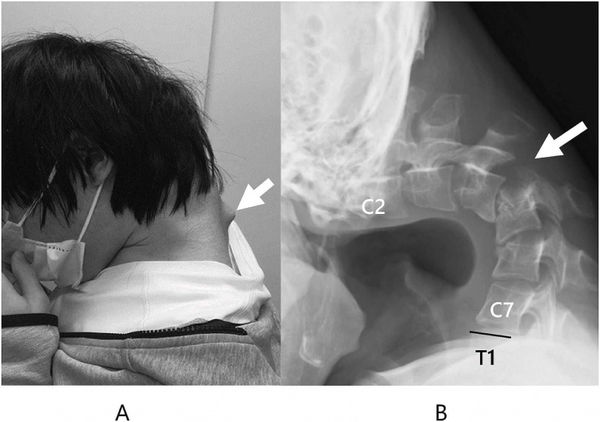

(东京18日综合电)日本一名25岁男子由于长期低头玩手机游戏,导致颈部肌肉严重退化,罹患罕见的“头部下垂症候群”(Dropped Head Syndrome,俗称垂头症),造成他出现无法抬头、吞咽困难等症状。

每日邮报报导,《JOS Case Reports》期刊的病例显示,男子颈部疼痛长达半年,而且有无法抬头、吞咽困难等症状,导致他进食困难,体重明显下降。

医疗团队检查后发现,男子颈椎已经变形移位,而且出现疤痕组织,初时医疗团队尝试使用护颈支撑矫正,男子却感到麻木不适,于是改用外科手术治疗。手术过程中,医生切除部分变形的颈椎骨与疤痕组织,再植入金属螺丝与钢钉固定骨架。

手术6个月后,男子已经可以将头部维持在正常水平的位置,术后一年也没有复发,抬头和吞咽的问题已经明显改善。